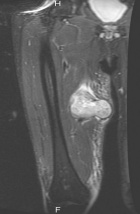

77 year old male c/o right thigh mass

Zoom image: Radiological image Radiological image.